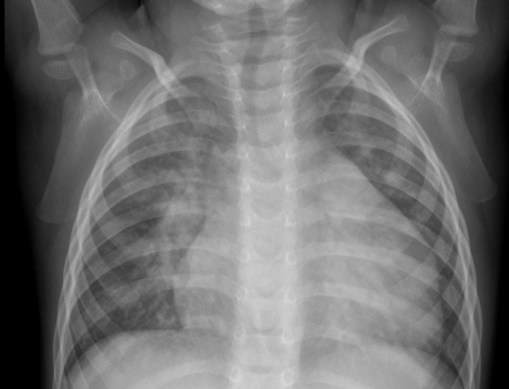

CASO: Operada de esofaguectomia y reconstrucción con coloplastia hace 3 meses. Sintomas de neumonía.

Hallazgos:

- De inicio llama la atención una densidad practicamente total del todo el hemitórax izquierdo, lo cual podría hacernos pensar que estamos ante una posible neumonía.

- Sin embargo el tórax está no está bien centrado, observar como la clavícula izquierda se encuentra casi en la mitad del pulmón, por tanto lo que vemos blanco es el mediastino ya que el tórax está rotado.

CENTRAJE:

El correcto centraje se determina comprobando que las extremidades internas de ambas clavículas equidistan de las apófisis espinosas vertebrales.

Mismo paciente, al cual esta vez se le ha tomado una radiografía en PA y en sedestación. Observar como las clavículas están equidistantes a las apófisis espinosas y como ha desaparecido el velamiento del pulmón izquierdo.

Por otra parte, paciente presenta una cardiomegalia y un discreto ensanchamiento del mediastino es probable relación con cambios postquirúrgicos.